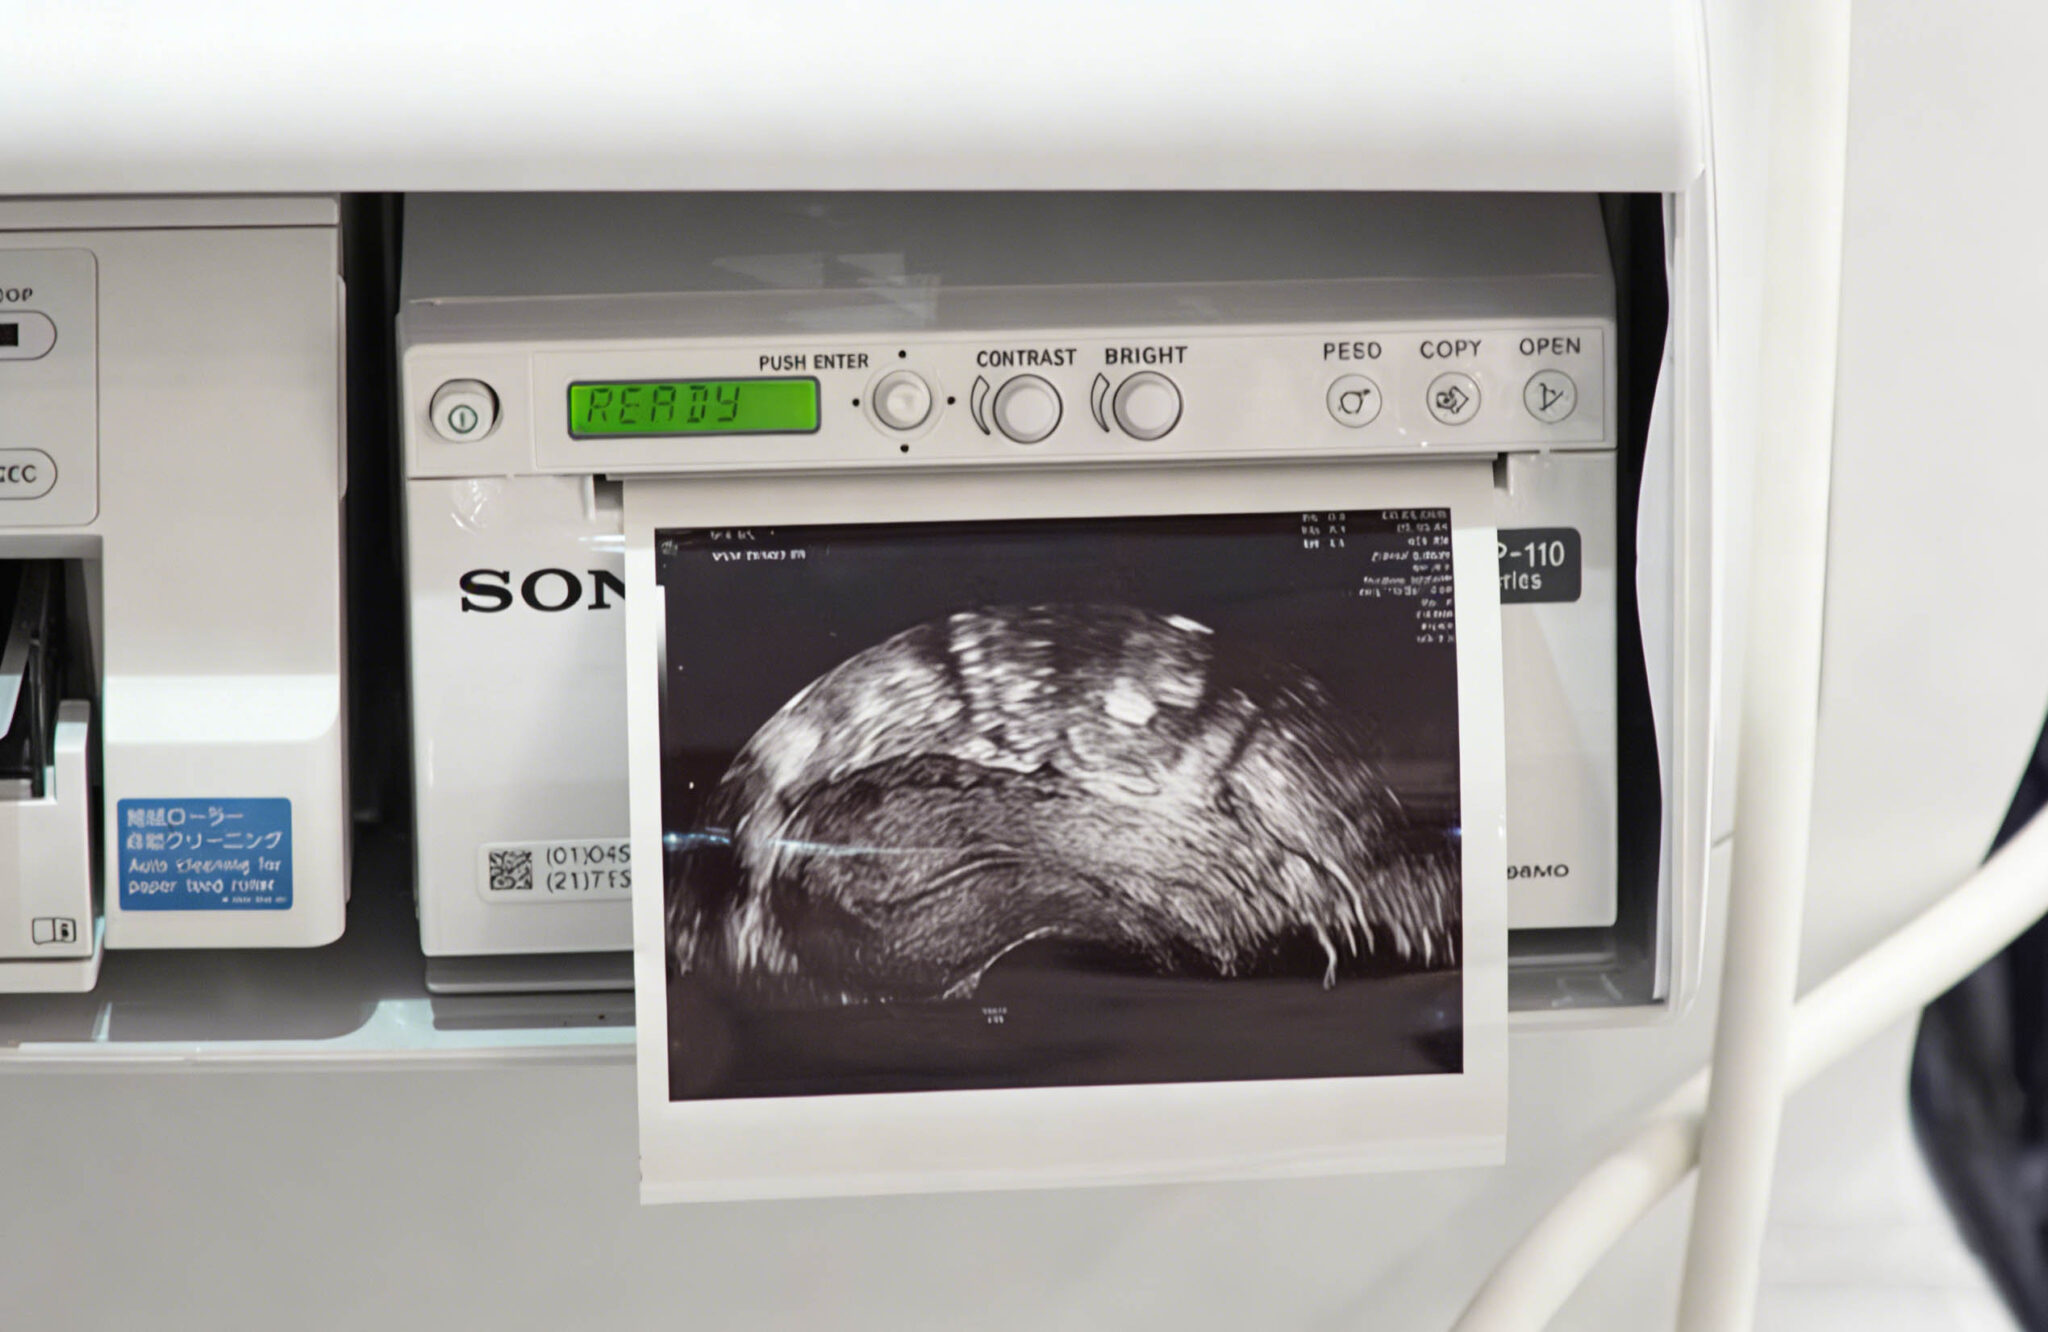

High density

Compatible with SONY UPP-110HD

This high-density A6 thermal printing media is ideal for a wide range of ultrasound applications, delivering clear and precise reproduction of subtle tonal gradations.